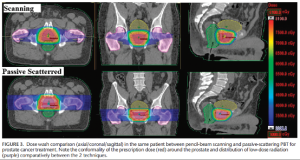

大多數在文獻中報導的接受質子治療的前列腺癌患者都使用的被動散射技術。質子束擁有獨特的物理特性,可以將絕大多數能量以一狹窄的截面在組織的某一固定深度沉積,而超出這一深度以外的劑量幾乎沒有。這一特性與光子束不同,光子束以指數方式在組織中衰減,有大量能量沉積在出射部位(圖1)。

被動散射(Passive Scattering)為了保證均勻照射到靶區,必須在預先定義的質子束的最小能量和最大能量之間調節,創造出一個“擴展布拉格峰(spread-outBraggpeak)”。在被動散射質子治療中,使用安裝好的射程調製器(rangemodulationwheel)來調整單能量的質子束射程(圖2A)。狹窄的質子束通過雙散射(doublescattering)系統向外擴展。定製化的黃銅擋塊用於將質子束塑形為靶區形狀(圖2B)。密集的組織(如,骨骼)相比稀疏的組織會散射更多的質子。

被動散射(Passive Scattering)筆形束掃描(PencilBeamScanning)

筆形束掃描(Pencil Beam Scanning)MD安德森的臨床經驗

MD安德森癌症中心具有成熟的質子治療的經驗,第一個報告了使用IMPT技術治療前列腺癌的臨床結局。研究入組了局部前列腺癌患者並進行2年隨訪,研究分為被動散射組和點掃描束組,前瞻性比較兩組患者的生活質量。患者在基線處和質子治療後每3到6個月完成EPIC問卷。共有226名接受被動散射治療,65名患者接受掃描束治療。通過EPIC生活質量量表評估腸道功能,被動散射組和點掃描束組在治療兩年後相比基線水平在腸道功能困擾上均有顯著減少(被動散射-7.7,筆形束-9.4)。兩組之間在醫生評估的毒性方面並無顯著差異,但使用點掃描束治療的患者報告的毒性事件更少。在24個月累積GU2度或以上的毒性發生率無顯著差異(被動散射14.2%,筆形束10.8%)。24個月累積GI2度或以上的毒性發生率無顯著差異(被動散射10.2%,筆形束7.7%)。在治療結束24個月氬離子凝固術的累積發生率為3.8%。被動散射組患者因直腸出血接受氬離子凝固術多於點掃描束組,然而此差異並未達到顯著差異。